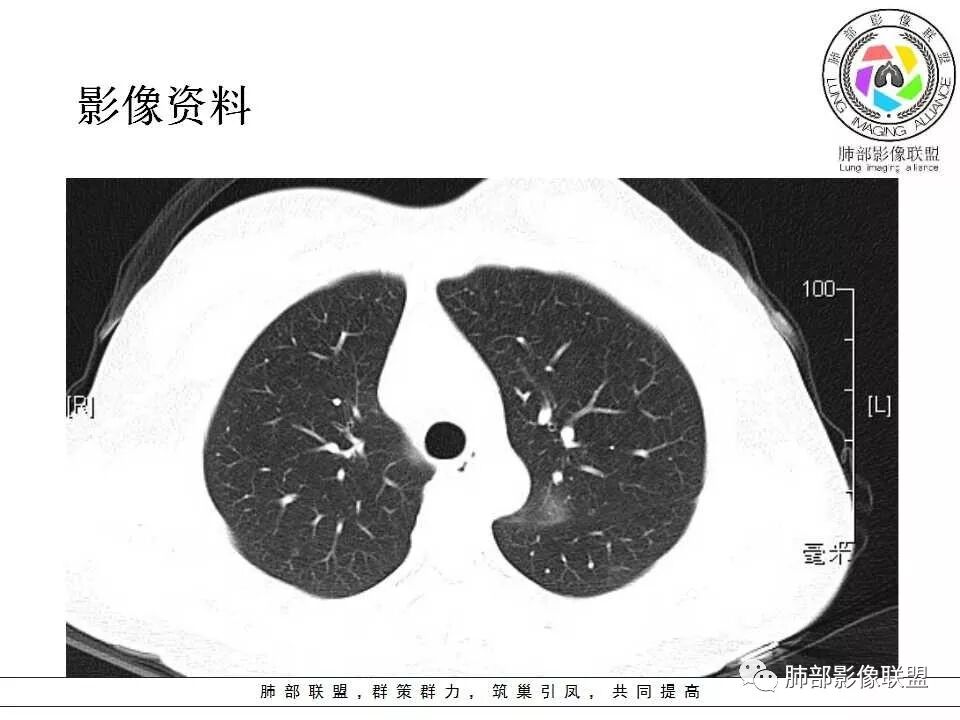

左肺门肿块,边缘光滑清晰,血管贴边,明显均匀强化,考虑PSP,鉴别类癌。

学习一下南大的诊断思路,左肺门区病灶,应该没跨叶,感觉都在上叶,强化密度均匀,边缘清晰,与支气管关系不大,常规考虑良性病变,PSP可能性大,鉴别CD,血管源性。但是一年增大怎么解释,不知道增大多少。

左肺病灶与支气管关系密切,类癌粘膜下生长,支气管略变窄,支气管外病变较大,符合冰山征表现,一年内有增长,考虑类癌,鉴别PSP,建议薄层重建。

我怎么又感觉跨叶间裂了,而且有胸膜尾征和可疑的指状突起,强化很明显,考虑SFT可能大,鉴别类癌和CD

年轻女性,左肺门区肿块,边缘光整,随诊有增大,恶性可能,类癌?鉴别psp、CD。

患者中年女性,发现左肺上叶占位,随访发现体积增大。胸部CT:左肺上叶尖后段实性占位,位于支气管旁,未见支气管阻塞,病灶边界清楚,边缘光滑,增强可见病灶均匀强化,血管贴边,考虑良性病变,PSP?

左肺上叶后段紧贴斜裂结节影,支气管通畅,斜裂无移位,说明病灶来源斜裂可能,强化密度均匀,边缘清晰,考虑良性病变,PSP可能性大,鉴别CD。

青年女性,慢性病程,实验室指标末提及,左肺门区肿块,边缘光滑,无明显分叶,周围清晰,增强明显强化,血管贴边,复查有增大,考虑良性或低度恶性病变,PSP?

患者中年女性,发现左肺上叶占位1年余入院,随访发现体积增大。胸部CT:左肺上叶尖后段近肺门及叶间裂实性类圆形结节,病灶边界清楚光滑,增强可见病灶明显均匀强化,其旁未见支气管堵塞。综合考虑良性病变,孤立性纤维瘤可能,鉴别巨大淋巴结增生症及硬化性肺细胞瘤。

青年女性,左肺门占位,边缘光滑,强化均匀,考虑为良性病变,PSP可能,近期复查增大,不除外恶性病变。

年轻女性,体检发现,左肺上叶近肺门处结节,边缘光滑,均匀明显强化,血管贴边,支气管无关,考虑PSP。

中年女性,发现左肺上叶占位。胸部CT:左肺上叶尖后段孤立卵圆形实性病灶,位于支气管旁,边界清楚,边缘光滑,血管贴边,肺动脉为主征,增强扫描明显均匀强化。考虑:PSP?鉴别CD、类Ca。

青年女性,左肺门占位。定位:跨叶间裂,下叶邻近支气管推压,考虑肺外病变。影像表现:血管贴边,边缘光滑,强化均匀,考虑良性病变,PSP可能大,鉴别CD。

左肺上叶类圆形实性病灶,边缘光滑,可见血管贴边征,病灶与左肺上叶支气管关系密切,左肺动脉相对增粗,增强病灶均匀强化,常规考虑PSP,其次神经内分泌肿瘤不排除。

厚层,只有动脉期。左肺门占位,边界清,动脉期强化比较明显,后段支气管不明确,考虑恶性,类癌可能。psp渐进性强化,动脉期好像没这么明显。

年轻女性,左肺门肿块,边缘光滑,密度较均匀,增强后肿块明显均匀强化,血供丰富,病史提示一年明显增大,也说明富血供,常规考虑PSP,类癌待排。

年轻女性,边缘光滑圆形肿块,均匀强化,血管贴边儿,常规考虑硬化性肺细胞瘤(PSP)。不放心的地方就是幻灯第22幅,似乎有一个小尾巴。巨淋巴结增生症(CD)及类癌待排。CD这个部位可以,但是相对少见的多。类癌的话强化可以,但是形态太规整了,似乎也不符合。潘老师还说过一个糖瘤,忘记长啥样儿了。

中年女性,查体发现,偶有咳嗽,左肺上叶近肺门肿块,边缘光滑,密度均匀,有强化,与支气管关系不清,有血管贴边,随访有增大,还是先考虑低度恶性肿瘤,类癌可能,鉴别psp。

青年女性,一年前发现肺结节,复查有增大,未见近期片对比,定位:左肺上叶左肺门旁见实性类圆形结节,边界清晰光整,有部分分叶征,增强有均匀强化,与左上叶后段支气管关系不好判断,左上叶后段支气管未显示,堵塞?狭窄?需冠矢状面看看,定性:常规考虑良性或低度恶性肿瘤,典型的类癌或硬化性肺细胞瘤psp可能,神经源性或神经内分泌肿瘤、巨淋巴结增生症CD不除外,转移瘤、孤立性纤维瘤待排,建议HRCT或支气管镜检查。

年轻女性,左肺门区占位,斜裂推移未跨叶,类圆形,增强扫描明显强化,和支气管关系显示不是太清楚,感觉关系不是太密切,未见阻塞性炎症,一年后有长大,首先考虑PSP,鉴别类癌,SFT。

左肺门区肿块,形态规则,边缘光滑,密度均匀,未见支气管截断,增强后均匀强化,血管似有贴边,年轻女性,考虑PSP,鉴别:CD,副节瘤。

36岁女性,发现左肺占位1年,时有干咳。CT:左肺门(上叶尖后段?)类圆形结节,边界清,靠前边缘似有GG0,近肺门侧与血管密切接触,似有小凸起,增强见明显均匀强化,似有条片状影往肺门侧血管钻。图片有点少,病灶与支气管的关系看不清(目前的图片与支气管不密切)。随诊结节增大,整体考虑典型类癌可能性大,鉴别硬化性肺细胞瘤。